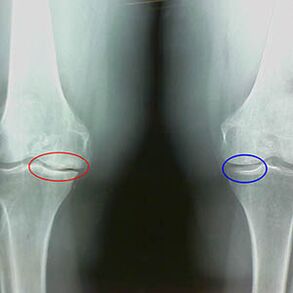

Ранни x -ray характеристики на втория етап на артрозата на коляното:

- заострените ръбове на междуградските туберкули на пищяла, където е прикрепен кръстосания лигамент;

- стесняване на ставната пропаст от медиалната страна;

- Точените ръбове на кондилите на костите от медиалните страни, по -рядко в странични - в зависимост от развитието на деформацията на валгус или вариант на ставите.

За втория етап в Ларсен Стесняване на празнината на ставите с повече от 50% е характерно, но това може да бъде проверено само в динамика или сравнение с различна от фуга.

Рентгенографията показва наличието на остеофити, промяна в пространството между костите на бедрената кост и пищяла, което показва загубата на хрущял в коляното. Понякога x -рината на колянните стави показва значителни признаци на износване на хрущяла, но пациентите не изпитват значителна болка.Напротив, артрозата на първия етап може да наруши функцията на коляното, тъй като причината за болката са хипотонични мускули.